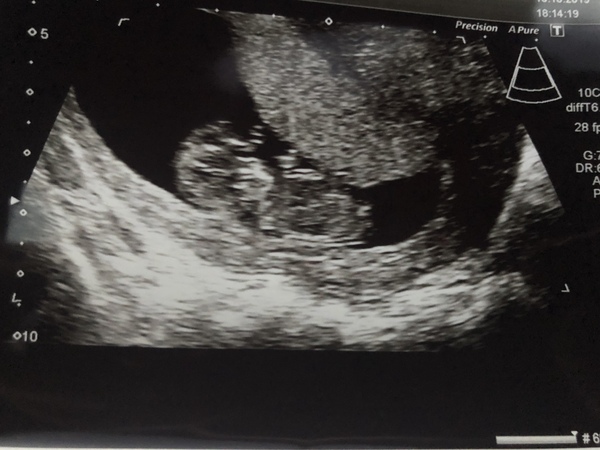

Hello 😊 @helensss the scan went well! Heartbeat found, here is little baby! Measuring 10+4 so I am 10 days behind LMP expected and about 6mm too small to have the screening tests so I’ll be asked back in about 10 days time! I have also booked the harmony test for next weds! I’m so relieved and it’s starting to feel real now. The baby looks so much more like a baby! Also was given a flu jab! Thanks to all those who wished me well 💕

@Sunshine8888 fantastic news and brilliant scan photo, amazing to see when I checked in this evening. I'll fall asleep with a smile on my face after seeing that, just amazing 🙏

@Sunshine8888 i love the picture. it makes it so real. is it possible to think it's a lovely baby 😍 already xxx so so happy

Ohh @Sunshine8888 what a beautiful scan picture. You must have felt so emotional. EPU are scanning me at 10+2 on the 29th, I’m praying I’ll see something similar to your scan. Has filled me with smiles this evening.

Lovely scan pic x so happy all went well x

@Sunshine8888 Congratulations on your beautiful scan. 🥰

Wohooo! Congratulations @Sunshine8888 !!! What a gorgeous photo of your little love 💖 Having had the dating scan are you gonna go public with the news now? I can't wait for it to not be a secret anymore! It genially feels a lifetime! I have my first midwife app tomorrow 😬